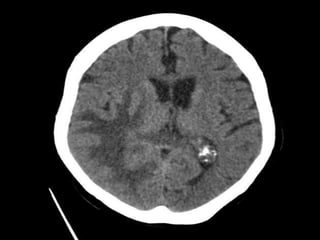

Hyperdensities

• Blood.

• Clot

• Calcium.

• Prosthesis.

• Contrast uptake.

• Choriod plexsus calcification and bone are the

do main hyperdensities that are present in

normal CT.